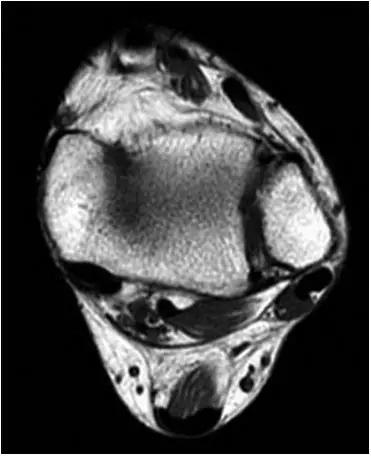

①踝关节外侧沟内异常软组织

②前胫腓韧带(AITFL)异常肥厚

T1WI FS C+

异常增厚的前胫腓韧带